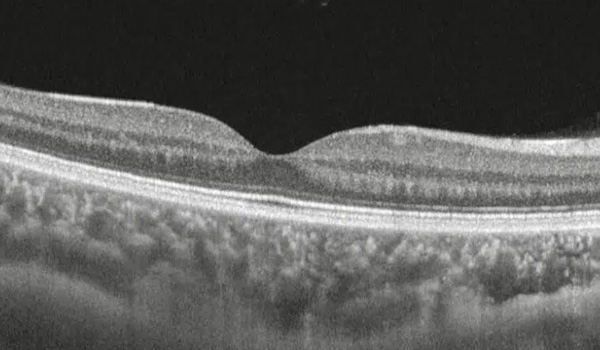

Manejo clínico de agujero macular

Evaluamos y tratamos quirúrgicamente agujeros en la mácula que generan visión central borrosa o distorsionada, con técnicas que promueven su cierre y recuperación visual.